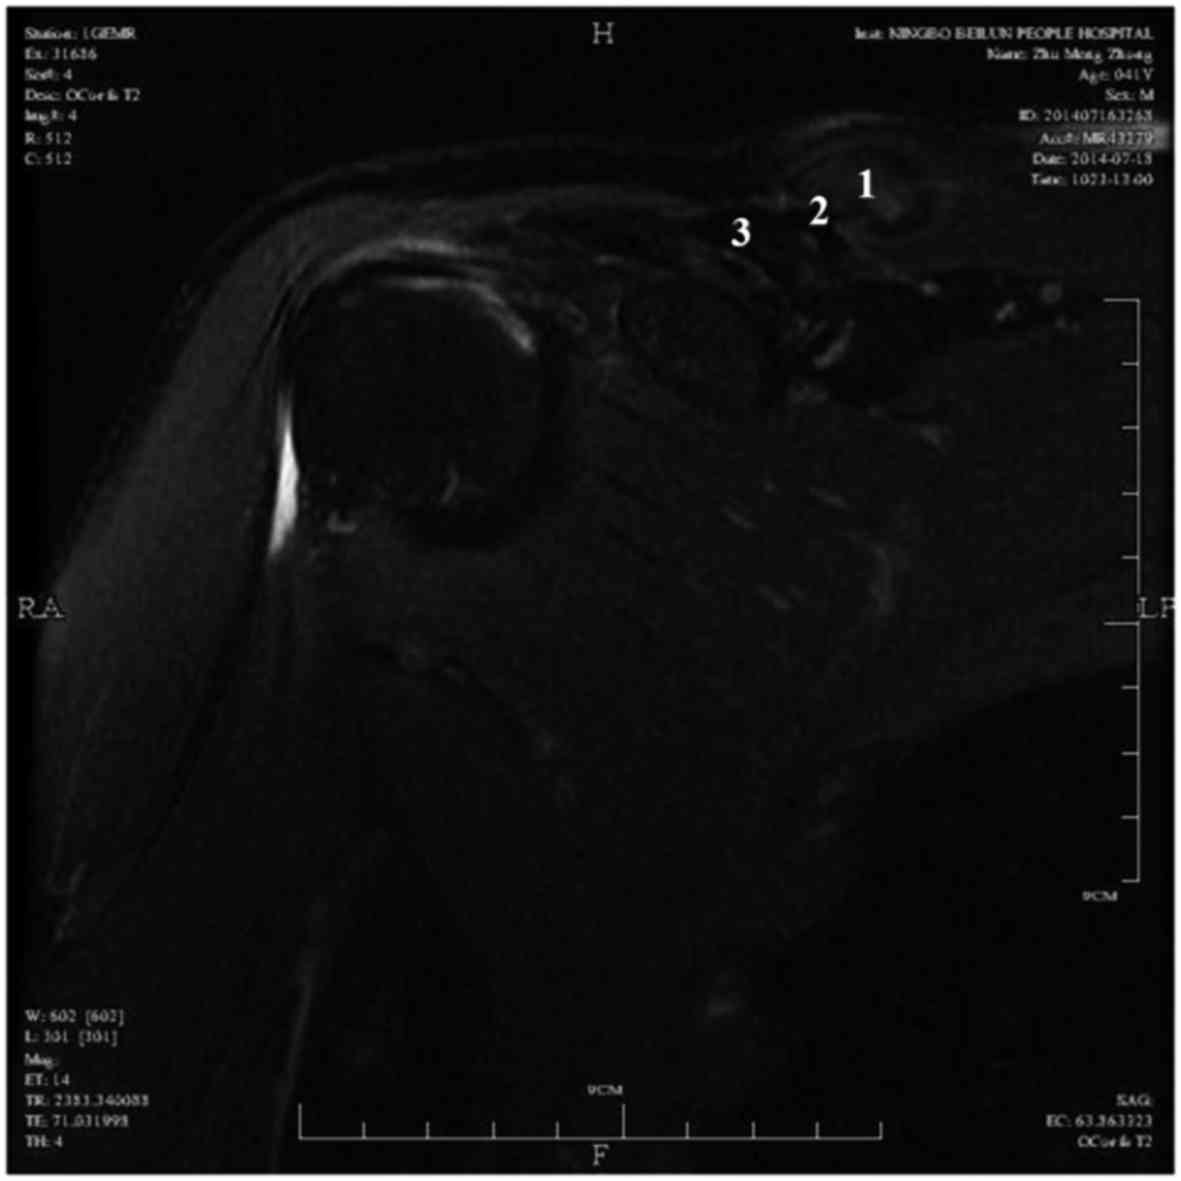

Radiographic examination revealed that the mass was located in the middle of clavicle, and its base intensity was similar to that of the clavicle; thus, the mass was initially suspected to be an osteochondroma (Fig. 1). On magnetic resonance imaging (MRI), the mass consisted of 3 layers (Fig. 2): The surface was encased in adipose tissue and the middle layer was osseous tissue; the base was fixed to the clavicle, but was not associated with clavicular marrow cavity. On T1- and T2-weighted images, the surface adipose tissue exhibited a high signal, while the core bone tissue exhibited a low signal.

Figure 2.

Coronal MR images showing a well-circumscribed soft tissue mass with low signal intensity on T2-weighted images. The mass was composed of a fat cap (1) and a large osseous base (2), and was adherent to the right clavicle (3).

Parosteal lipoma may occasionally be misdiagnosed as osteochondroma, when there is association with the underlying bone (12). In this case, the X-ray examination raised the suspicion of osteochondroma. On MRI, the mass was characterized by high signal intensity on T1-weighted images, with low signal of the bone layer. The mass exhibited low signal intensity on T2-weighted images (Fig. 2).